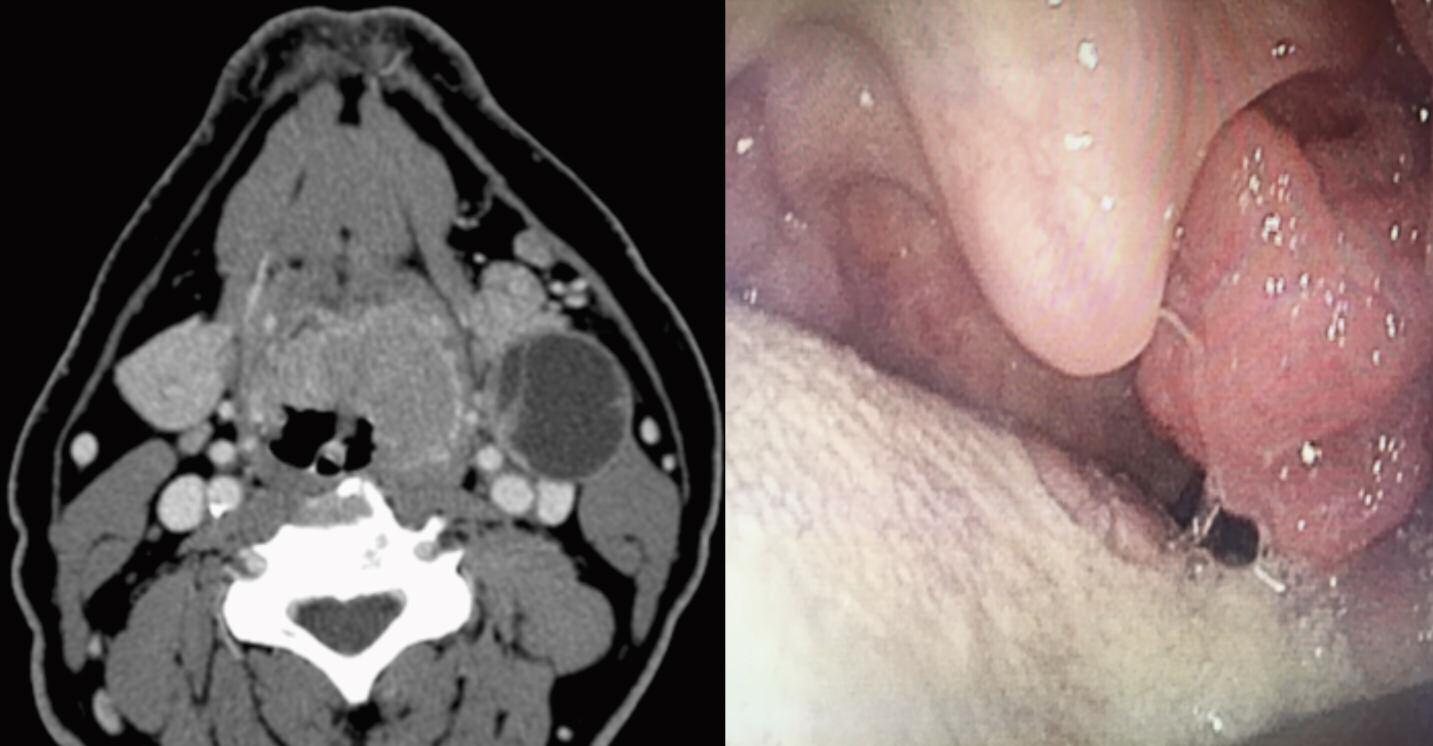

Dall’altro, il carcinoma orofaringeo correlato a HPV è un’entità nosologica che si è andata sempre più delineando negli ultimi dieci anni. Fino ad allora, il virus era stato implicato nella patogenesi di altre malattie di interesse ORL, quali alcuni papillomi schneideriani naso-sinusali, le lesioni verrucose del cavo orale e la papillomatosi respiratoria ricorrente. Sotto il profilo biologico queste malattie sono legate all’infezione di sierotipi virali cosiddetti “a basso rischio” di trasformazione maligna ossia HPV-6 e HPV-11. Successivamente, l’analisi molecolare ha identificato HPV “ad alto rischio” (HPV 16, 18, 31, 33) nelle lesioni maligne orofaringee, sierotipi spesso chiamati in causa per lo sviluppo delle lesioni precancerose e cancerose della cervice uterina, del pene e della regione anale. Gli studi epidemiologici hanno mostrato che i pazienti colpiti sono più spesso maschi caucasici, con età media di 50 anni e bassa prevalenza di consumo di tabacco. Questi tumori colpiscono tipicamente la regione orofaringea (Figura 2) in cui il carcinoma si presenta come forma poco cheratinizzante, di aspetto basaloide e con metastasi linfonodali che presentano solitamente un aspetto cistico.

Come nella cervice uterina, l’attività sessuale oro-genitale, oro-anale e persino oro-orale (“deep kissing”), specialmente con partner multipli, rappresenta un importante fattore di rischio in quanto fonte di microtraumi che possono favorire l’infezione a livello dello strato basale dell’epitelio. Le tonsille linguali e palatine sono particolarmente affette in quanto al fondo delle cripte la sottile interfaccia linfoepiteliale (Figure 3 a/b) rende le cellule molto più suscettibili all’infezione rispetto ad altre sedi ORL caratterizzate da uno spesso epitelio pluristratificato squamoso o respiratorio.

Sotto il profilo clinico-terapeutico, i carcinomi orofaringei HPV-correlati si presentano spesso in stadi avanzati e con particolari caratteristiche cliniche e prognostiche al punto che i gruppi internazionali AJCC e UICC, nella più recente edizione del TNM, hanno sviluppato una classificazione specifica per tali neoplasie HPV correlate. Non di rado, le metastasi cervicali linfonodali sono il primo segno di presentazione (Figura 4), eppure la prognosi è nettamente migliore, a parità di stadio, rispetto alle forme p16 negative (sopravvivenza a tre anni, 82.4% se p16+ vs 57.1% se p16-). Particolarmente efficace è il trattamento combinato radio-chemioterapico che presenta meno complicanze rispetto alla chirurgia. Sulla base di tali dati favorevoli, negli ultimi anni diversi autori stanno cercando di valutare l’efficacia di trattamenti meno tossici omettendo, per esempio, la chemioterapia (cd. protocolli di de-intensificazione).